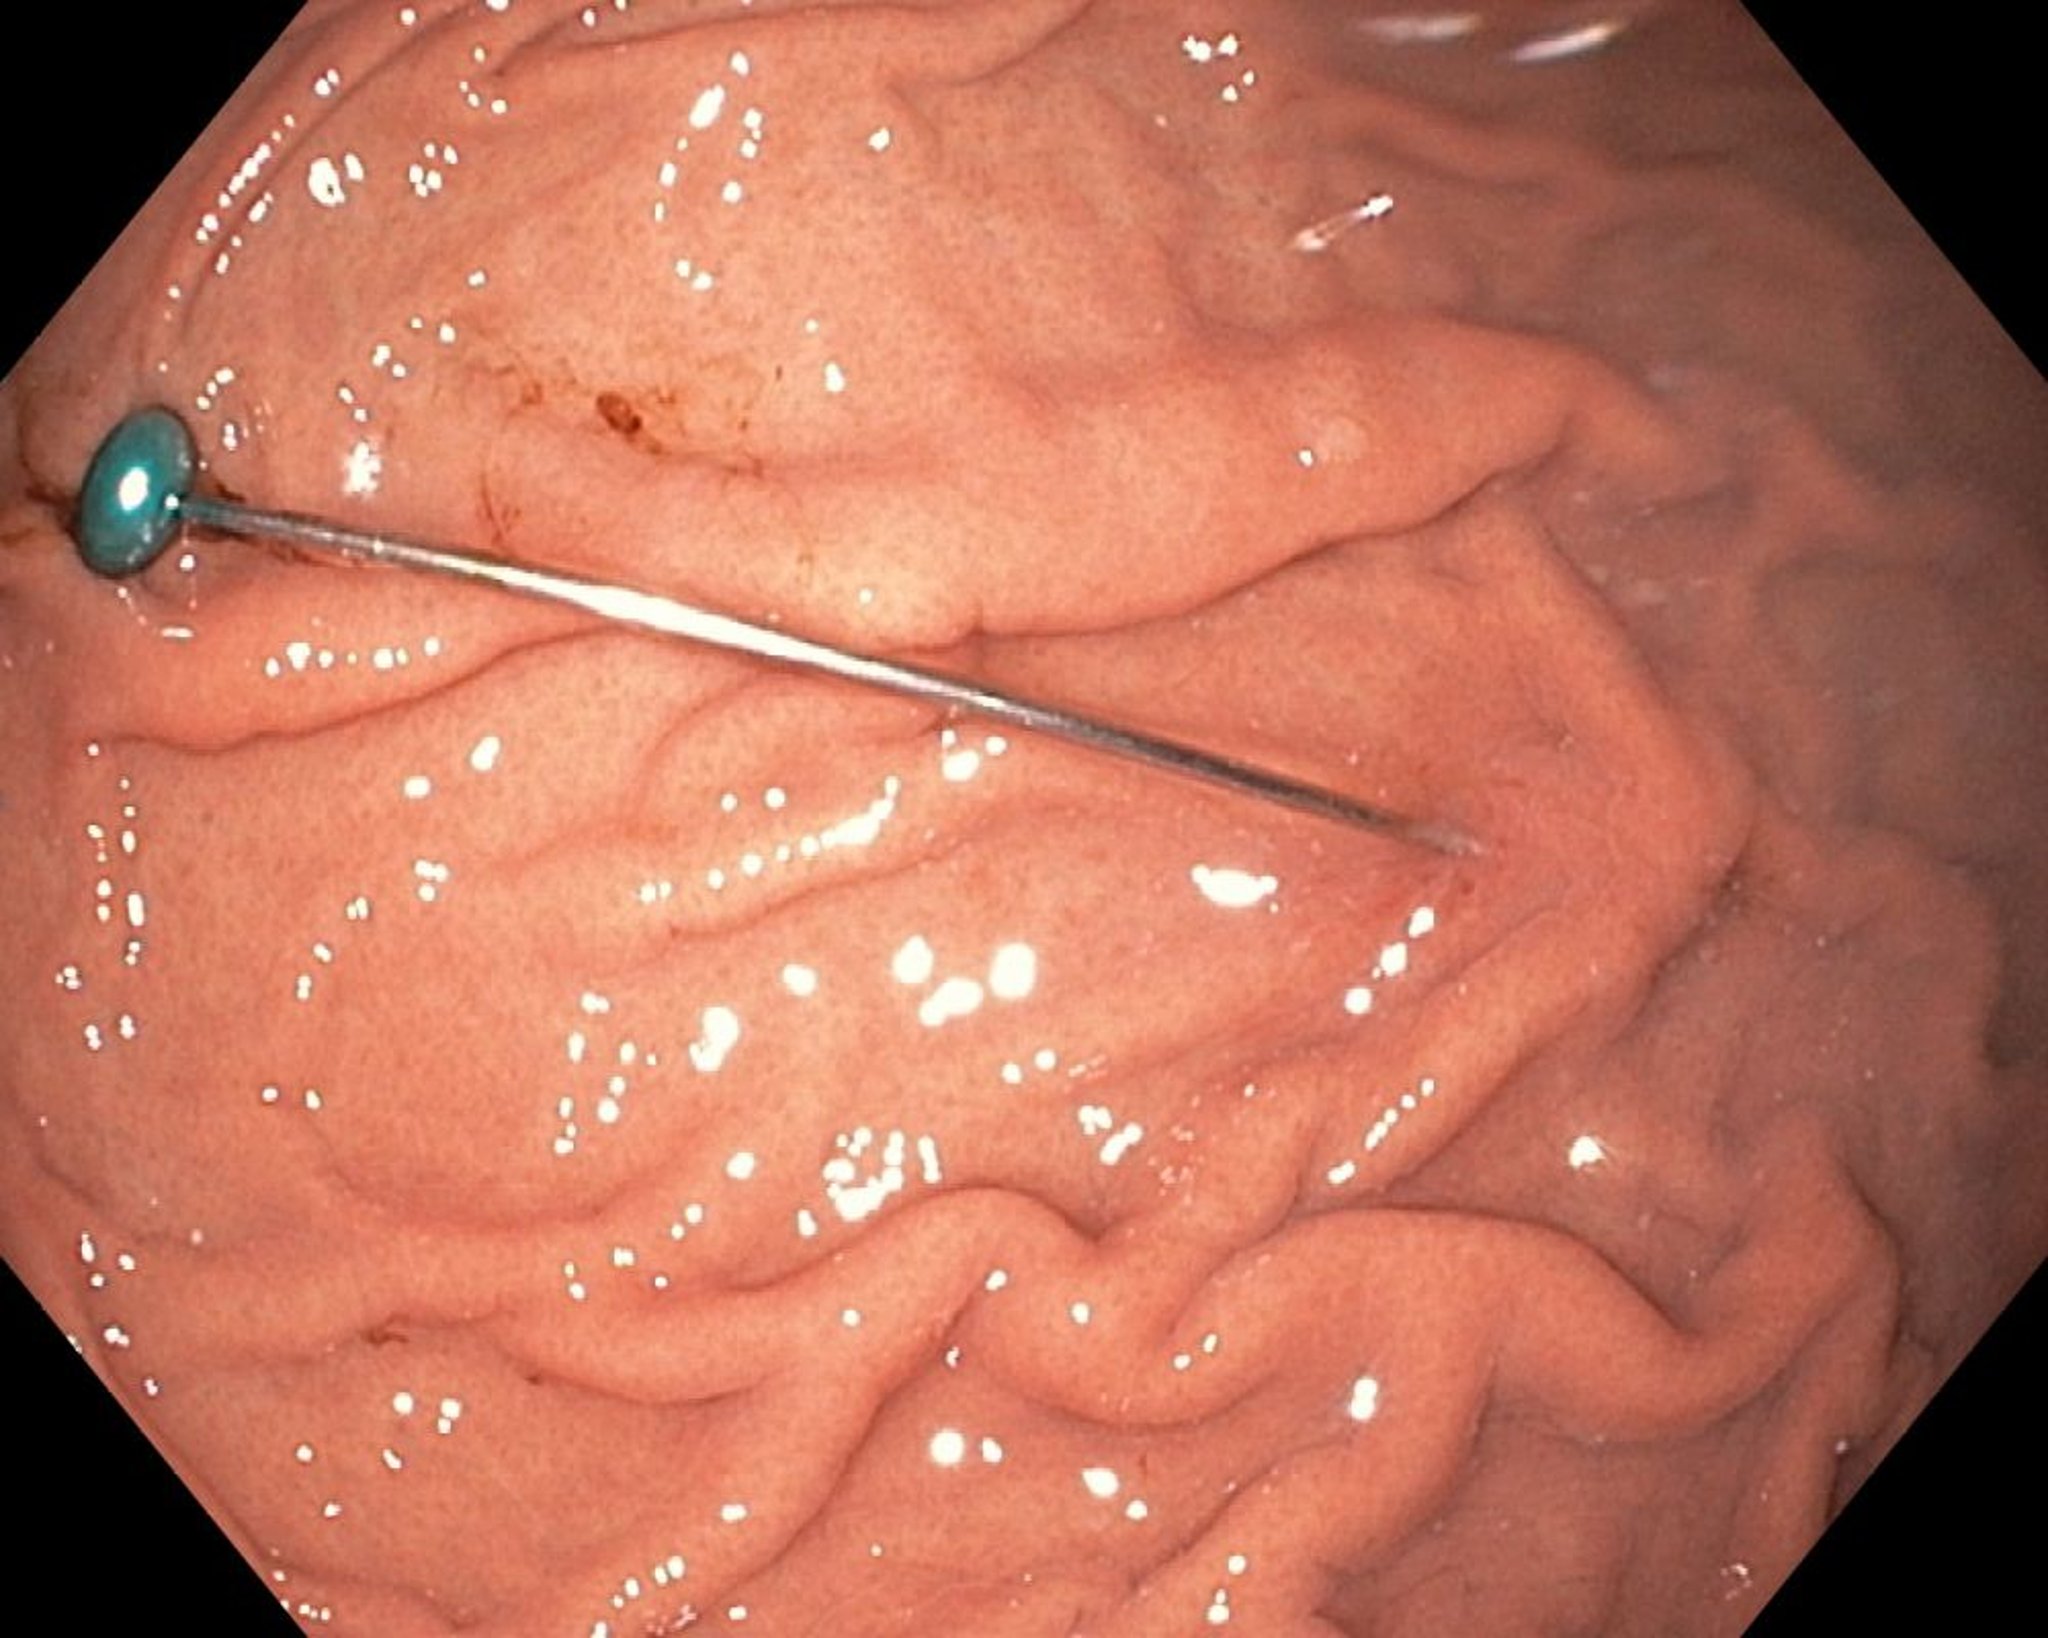

Острое инородное тело в желудке (эндоскопия)

На этом снимке показано острое инородное тело в желудке.

Снимок предоставлен доктором медицины Удай Шанкар (Uday Shankar, MD).